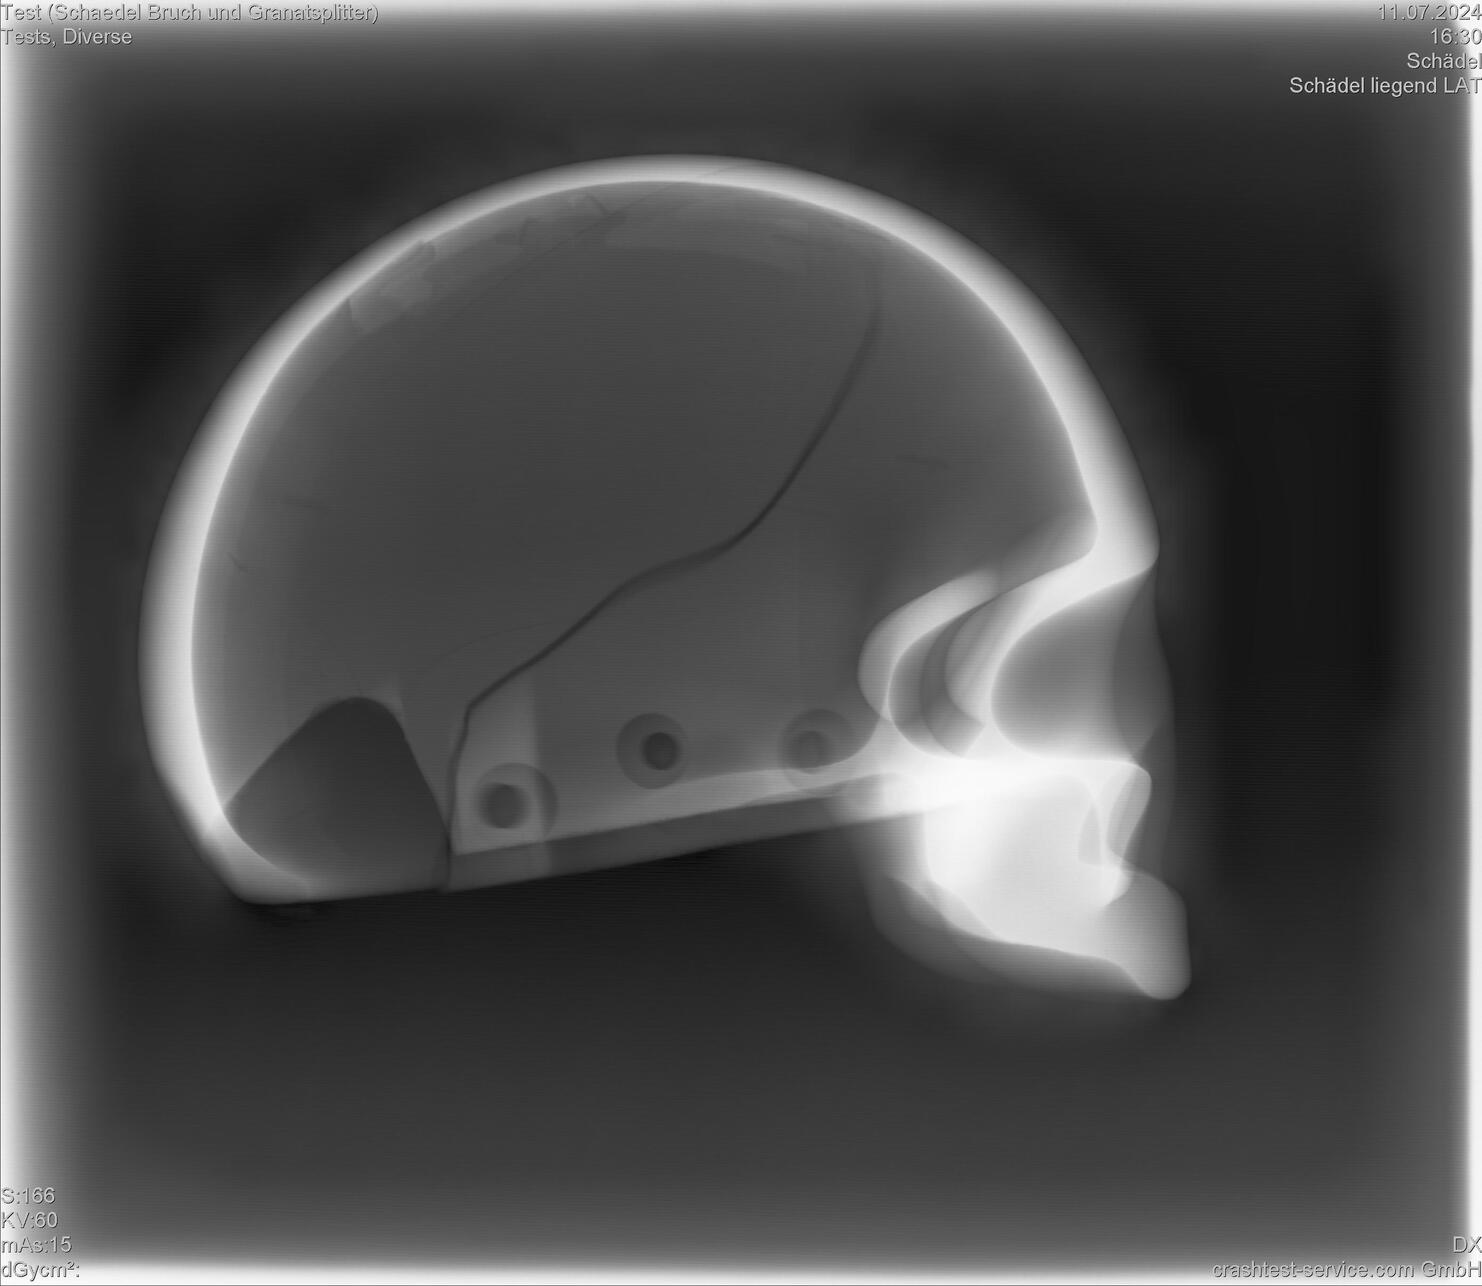

Der biofidele PRIMUS-Dummy ist der weltweit erste röntgenfähige Dummy – und genau das ist es, was den Vergleich zwischen realen und nachgestellten Verletzungen bzw. Beschädigungen so besonders macht.

Direkt nach einem Crashtest können durch medizinisches Röntgen Beschädigungen an Knochen- und Gewebeteilen des PRIMUS-Dummys sichtbar gemacht werden. Durch diese direkten Einblicke können so Rückschlüsse auf reale Verletzungen gezogen werden und ermöglichen darüber hinaus eine Einstufung in die vereinfachte Verletzungsskala (Abbreviated Injury Scale (AIS)).

Auswertung der Röntgenbilder, PRIMUS breakable

Schädelbruch